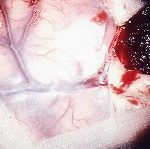

No.359 手術中

No.359 手術後

出血既往があり。2回の手術前血管内手術の後に、

Lateral transpeduncular approachにより再々出血予防を目的に

摘出手術を行う。完全摘出であることを確認した。

手術による合併症や後遺症なしで退院した。経過良好。